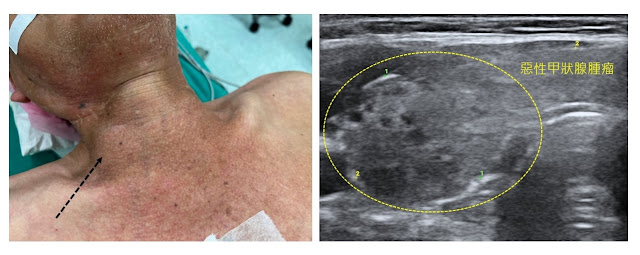

惡性腫瘤一般在超音波下邊緣會比較不規則,腫瘤的質地看起來也比較不均勻,且有時候會看到鈣化點,如果用超音波看血流也會比較亂,並長到腫瘤中間(不過張醫師覺得看血流的幫助不大,鈣化點是蠻有幫助的)。手術中會發現腫瘤跟周圍組織沾黏得比較緊,且有可能跟喉返神經黏住,在分開的過程會很費力,需要配合顯微鏡與神經探測器,慢慢的將腫瘤與神經做分離,但有時候在分離的過程中會拉扯到神經,容易造成術後聲帶暫時性或永久性麻痺。

| 上圖是一個甲狀腺惡性腫瘤的超音波影像,頸部外觀也可以看到一顆突起物,摸起來挺堅硬的。 |